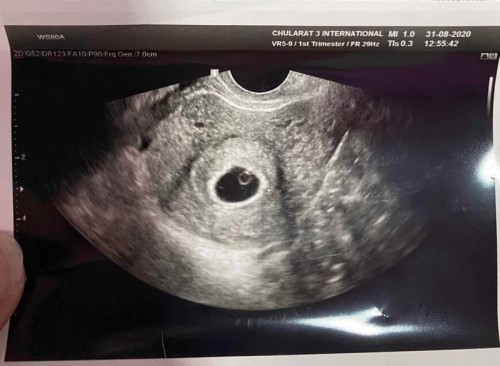

ที่เป็นกลมๆในถุงตั้งครรภ์ไม่ใช่เด็กหรอคะ นี้ภาพซาวด์ของเค้า หมอบอกว่าเป็นเด็กแค่ยังไม่เห็นหัวใจเพราะอายุครรภ์ยังน้อย

ขออนุญาติตอบตามประสบการณ์ตัวเองนะคะ ตอนเราท้องลม เราก็เคยถามหมอค่ะ ว่าในถุงคืออะไร หมอบอกว่าเหลือแต่ถุงไข่แดงค่ะ (เราสังเกตว่าจะอยู่ติดขอบถุงตั้งครรภ์) อีกอย่างถุงตั้งครรภ์จะโตตามอายุครรภ์ เมื่อถึงช่วงนึงร่างกายจะรับรู้เองค่ะว่า ในถุงไม่มีอะไร และจะเริ่มมีเลือดออกค่ะ เป็นกลไกปกติของร่างกายค่ะ สุดท้ายเราเลือดออกและขูดมดลูกค่ะ และตอนนี้ท้องใหม่แล้ว น้อง 28 สัปดาห์แล้วค่ะ